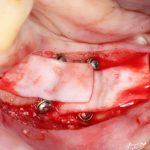

Кстати, обрати внимание на ширину альвеолярного гребня (левая картинка). Она чуть меньше 3 мм. Это объясняет, почему я засомневался в возможности установки имплантатов одновременно с остеопластикой. Понятно и без КЛКТ.

Возвращаемся к основной операционной области. Еще раз посмотрим на альвеолярный гребень, поофигеваем от его ширины и моих грандиозных планов:

Я зафиксировал костный блок практически без адаптации на несколько винтов. Обрати внимание, что винты находятся в зоне, где не планируется установка имплантатов. Фиксация должна быть надежной, поскольку мне еще предстояла подготовка лунок для имплантатов. Трех винтов для этого вполне достаточно.